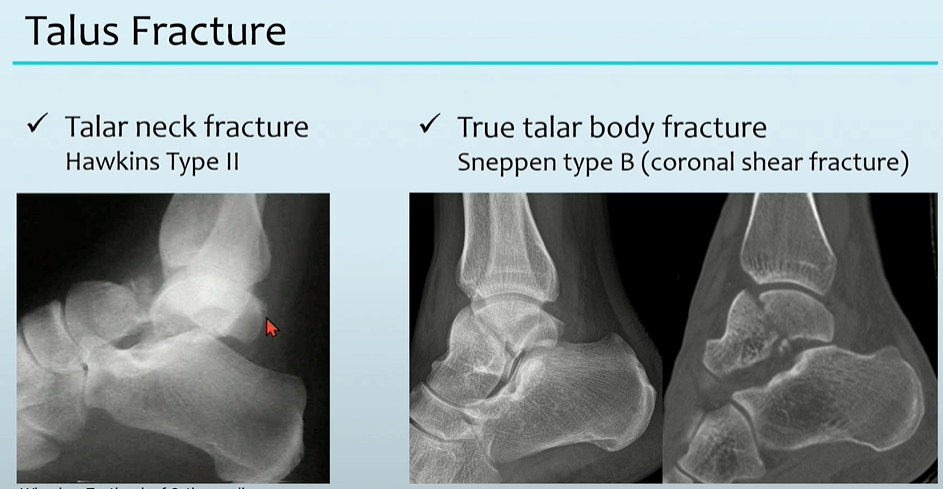

3. Talus Fracture